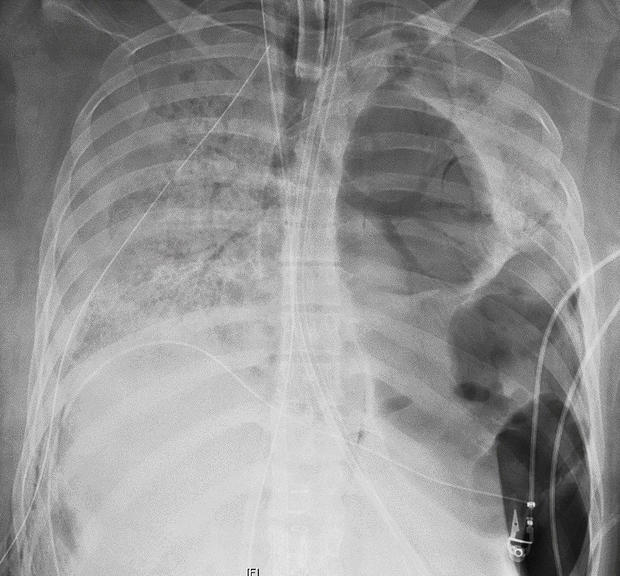

Слева - здоровые легкие, справа - легкие пациентки из Чикаго

Хирург Анкита Бхарат, которая проводила операцию, сообщила, что легкие девушки были все в дырах и практически слились с грудной клеткой.